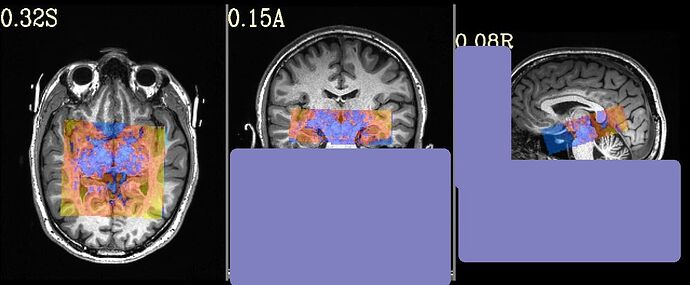

But when checking for EPI to Anat alignment, it looks like follows (almost like applying re-obliquing twice):

Where the DEOB doesn't seem to be correct.